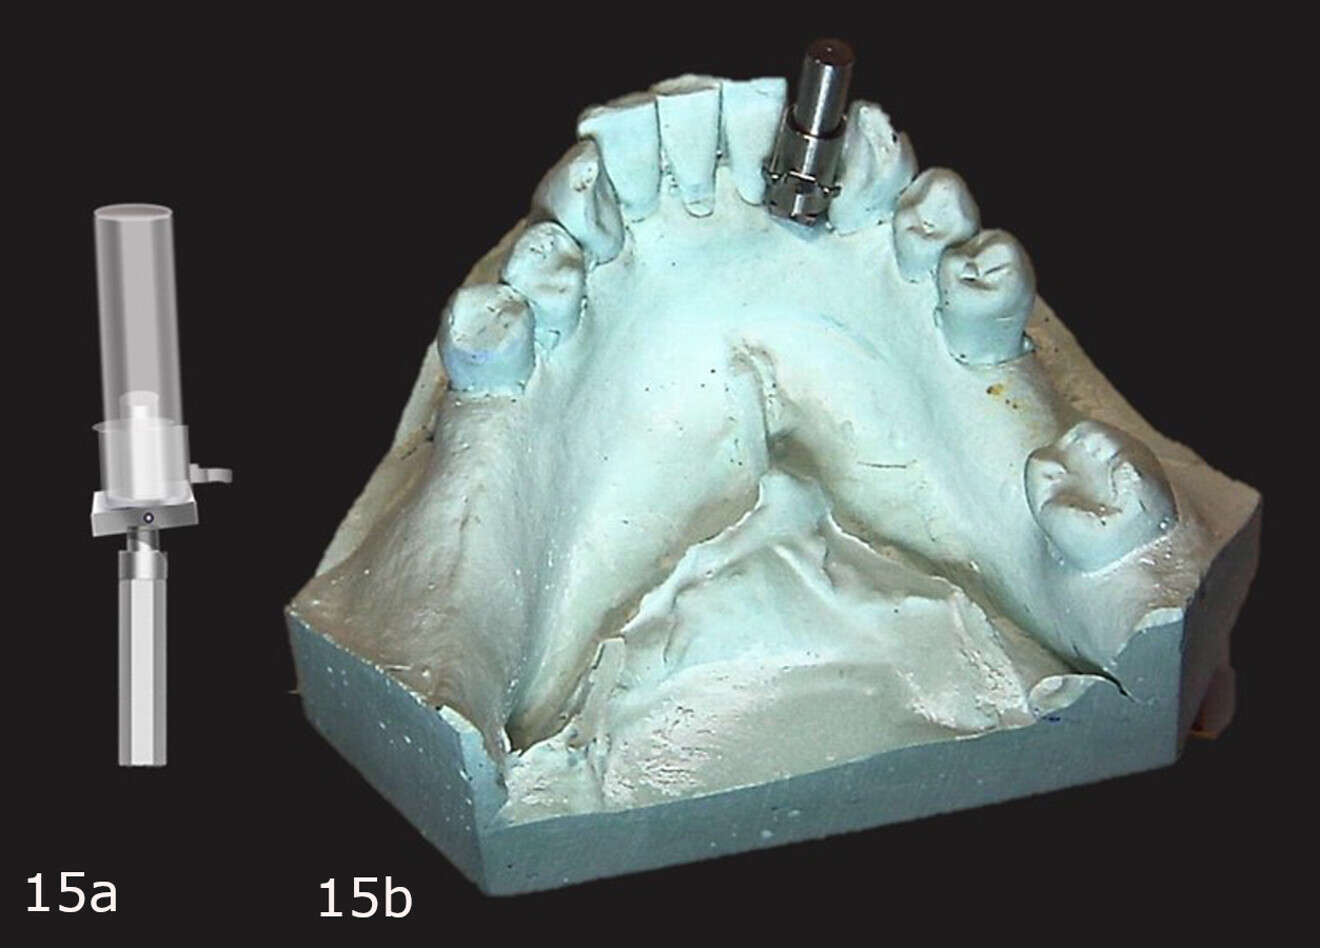

The conventional impression was utilised to create a stone cast to be used to fabricate a diagnostic guide. The 3/32 in. Guide Right pilot drill was utilised to create a guide hole in the planned implant site on the cast that was parallel to the adjacent teeth and centred in the extraction site (Fig. 3). A Guide Right one-piece guide post was inserted into the pilot hole on the cast (Fig. 4). Next, a Guide Right guide sleeve was inserted over the guide post with the retentive cleat positioned to the lingual aspect (Fig. 5). A light-polymerising resin (primopattern LC Gel, primotec) was placed over the cleat and then a roll of light-polymerising resin (primosplint, primotec) was placed on the lingual aspect of the teeth on the cast (Fig. 6). The resin was then pressed on to the lingual aspect of the teeth and the occlusal surfaces, light-polymerised and removed from the cast, creating the diagnostic guide (Fig. 7).

Figs. 3a–c: Pilot hole made in the cast at the planned implant site, paralleling it to the adjacent teeth and centring it in the site (a & c). Guide Right pilot drill (b).